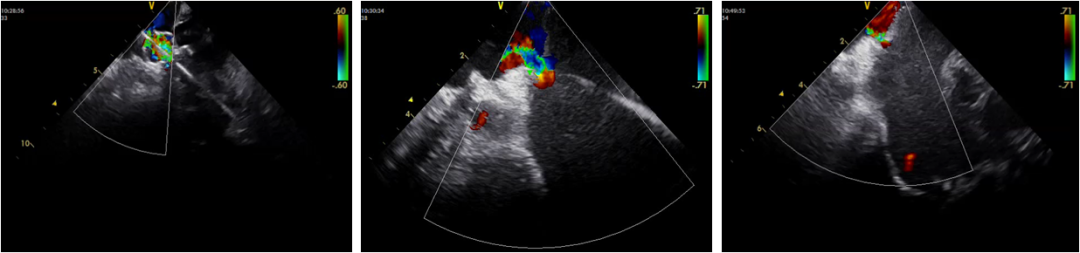

Case-1

• HFrEF

Case-2

• HFpEF

Case3

Case-4